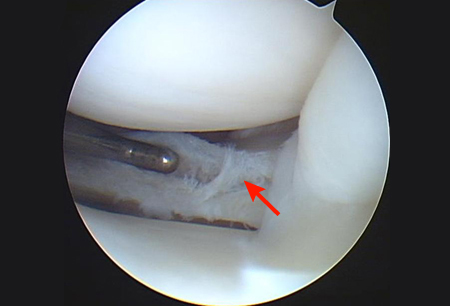

Arthroscopic view of horizontal cleavage tear of lateral meniscus (arrow)

From the collection of Dr Kevin R. Stone